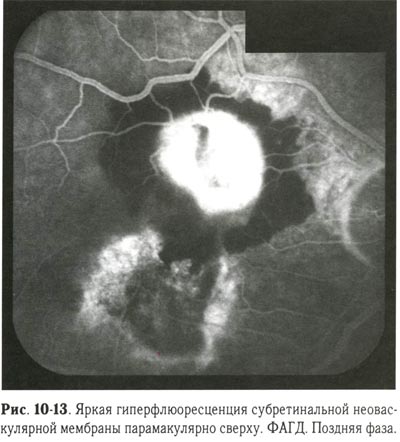

При коагуляции субретинальной неоваскулярной мембраны, расположенной в макулярной зоне, следует учитывать возможность снижения остроты зрения, о чём пациента нужно заранее предупредить. Коагуляцию начинают с нанесения коагулятов III степени по краю субретинальной неоваскулярной мембраны, затем переходят к сплошной черепицеобразной коагуляции мембраны. Наиболее щадящей для макулы считается коагуляция криптоновым лазером. Рекомендуется проведение контрольной ФАГД через 2-3 мес после лазерной коагуляции. Если полное рубцевание мембраны не достигнуто, то лазерную коагуляцию повторяют (рис. 10-13, 10-14).

Яркая гиперфлюоресценция субретинальной неоваскулярной мембраны парамакулярно сверху. ФАГД. Поздняя фаза. |